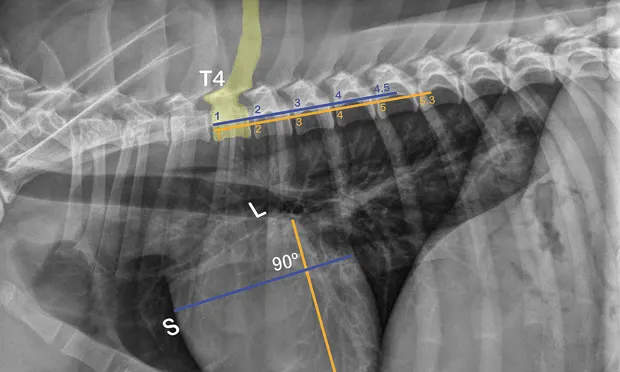

The ACVIM consensus statement on degenerative MVD recommends baseline thoracic radiography for dogs with a new murmur, then annually thereafter.6 For practitioners adhering to these guidelines, annual calculation of VHS and rate of change from previous imaging should become standard practice and may help identify those patients at higher risk of developing CHF in the coming year. Figure 2 illustrates annual radiographs taken in a patient with progressive cardiomegaly.

Progressive cardiomegaly noted on annual evaluations in a dog with MVD.